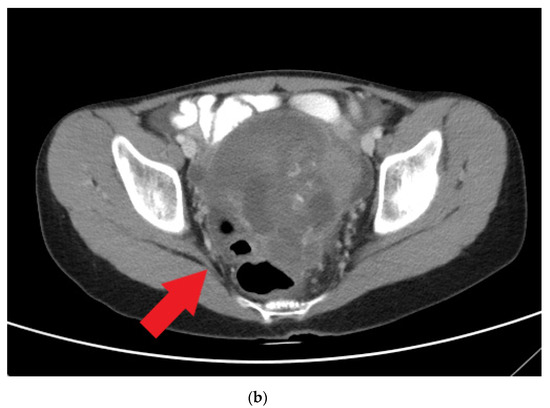

Frasier syndrome is a rare disease that affects the kidneys and genitalia. Patients who have Frasier syndrome develop nephrotic syndrome (NS) featuring focal segmental glomerulosclerosis (FSGS) that is resistant to steroid treatment in early childhood. Male patients can have female external genitalia (pseudo-hermaphroditism) [...] Read more.

Frasier syndrome is a rare disease that affects the kidneys and genitalia. Patients who have Frasier syndrome develop nephrotic syndrome (NS) featuring focal segmental glomerulosclerosis (FSGS) that is resistant to steroid treatment in early childhood. Male patients can have female external genitalia (pseudo-hermaphroditism) at birth and develop gonado-blastoma in their adolescence. Frasier syndrome is caused by mutations in the splice donor site at intron 9 of the Wilms’ tumor WT1 gene; these mutations result in an imbalanced ratio of WT1 protein isoforms and affect the development of the urogenital tract, podocyte function, and tumor suppression. Here, we report on a patient with long-term refractory NS who developed a malignant mixed germ cell tumor arising in a gonado-blastoma of the ovary 8 years after the onset of proteinuria. Full article